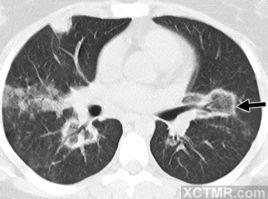

反暈征(reversed hato sign),是一個局灶性圓形弱毛玻璃區域,由幾乎完整的實性環包繞。

CT 表現:為一局灶性圓形磨玻璃區,圍繞完整的實變環,是一種少見的徵象。起初認為對診斷隱nUY影像園XCTMR.com原性肺泡炎有特異性,但隨後發現該徵象也見於類球孢子菌病的描述中。和暈征相似,當該徵象見於多種疾病後,可能失去其特異性。也見於暈征。

反暈征,又稱環礁跡象,首先在相對特異的隱機化性肺炎中描述,後來在其他一些感染性和非感染性疾病中也觀察到,包括少數幾例肺腺癌。

通常,我們發現結節尺寸增長與衰減增加有關。然而,該病例尺寸穩定的病灶出現緩慢且漸進性中央衰減增加,反暈征轉為暈征,在肺腺癌中觀察到。